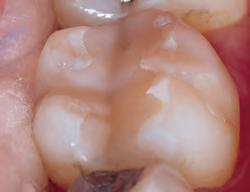

DISTO-OCCLUSAL CLINICAL CASE